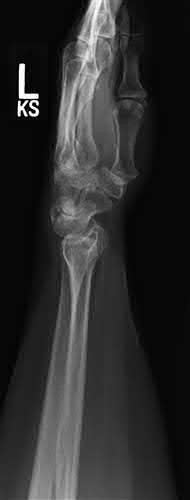

Question 10:

A 35-year-old male sustains a vertically oriented (Pauwels type III) basicervical femoral neck fracture. Which of the following fixation constructs offers the highest biomechanical stability for this specific fracture pattern?

Correct Answer: Sliding hip screw with an anti-rotation screw

Explanation:

Vertical fracture patterns (Pauwels III) experience high shear forces. A sliding hip screw (SHS) provides better resistance to vertical shear compared to cancellous screws. The addition of an anti-rotation (derotational) screw superior to the SHS provides optimal stability.